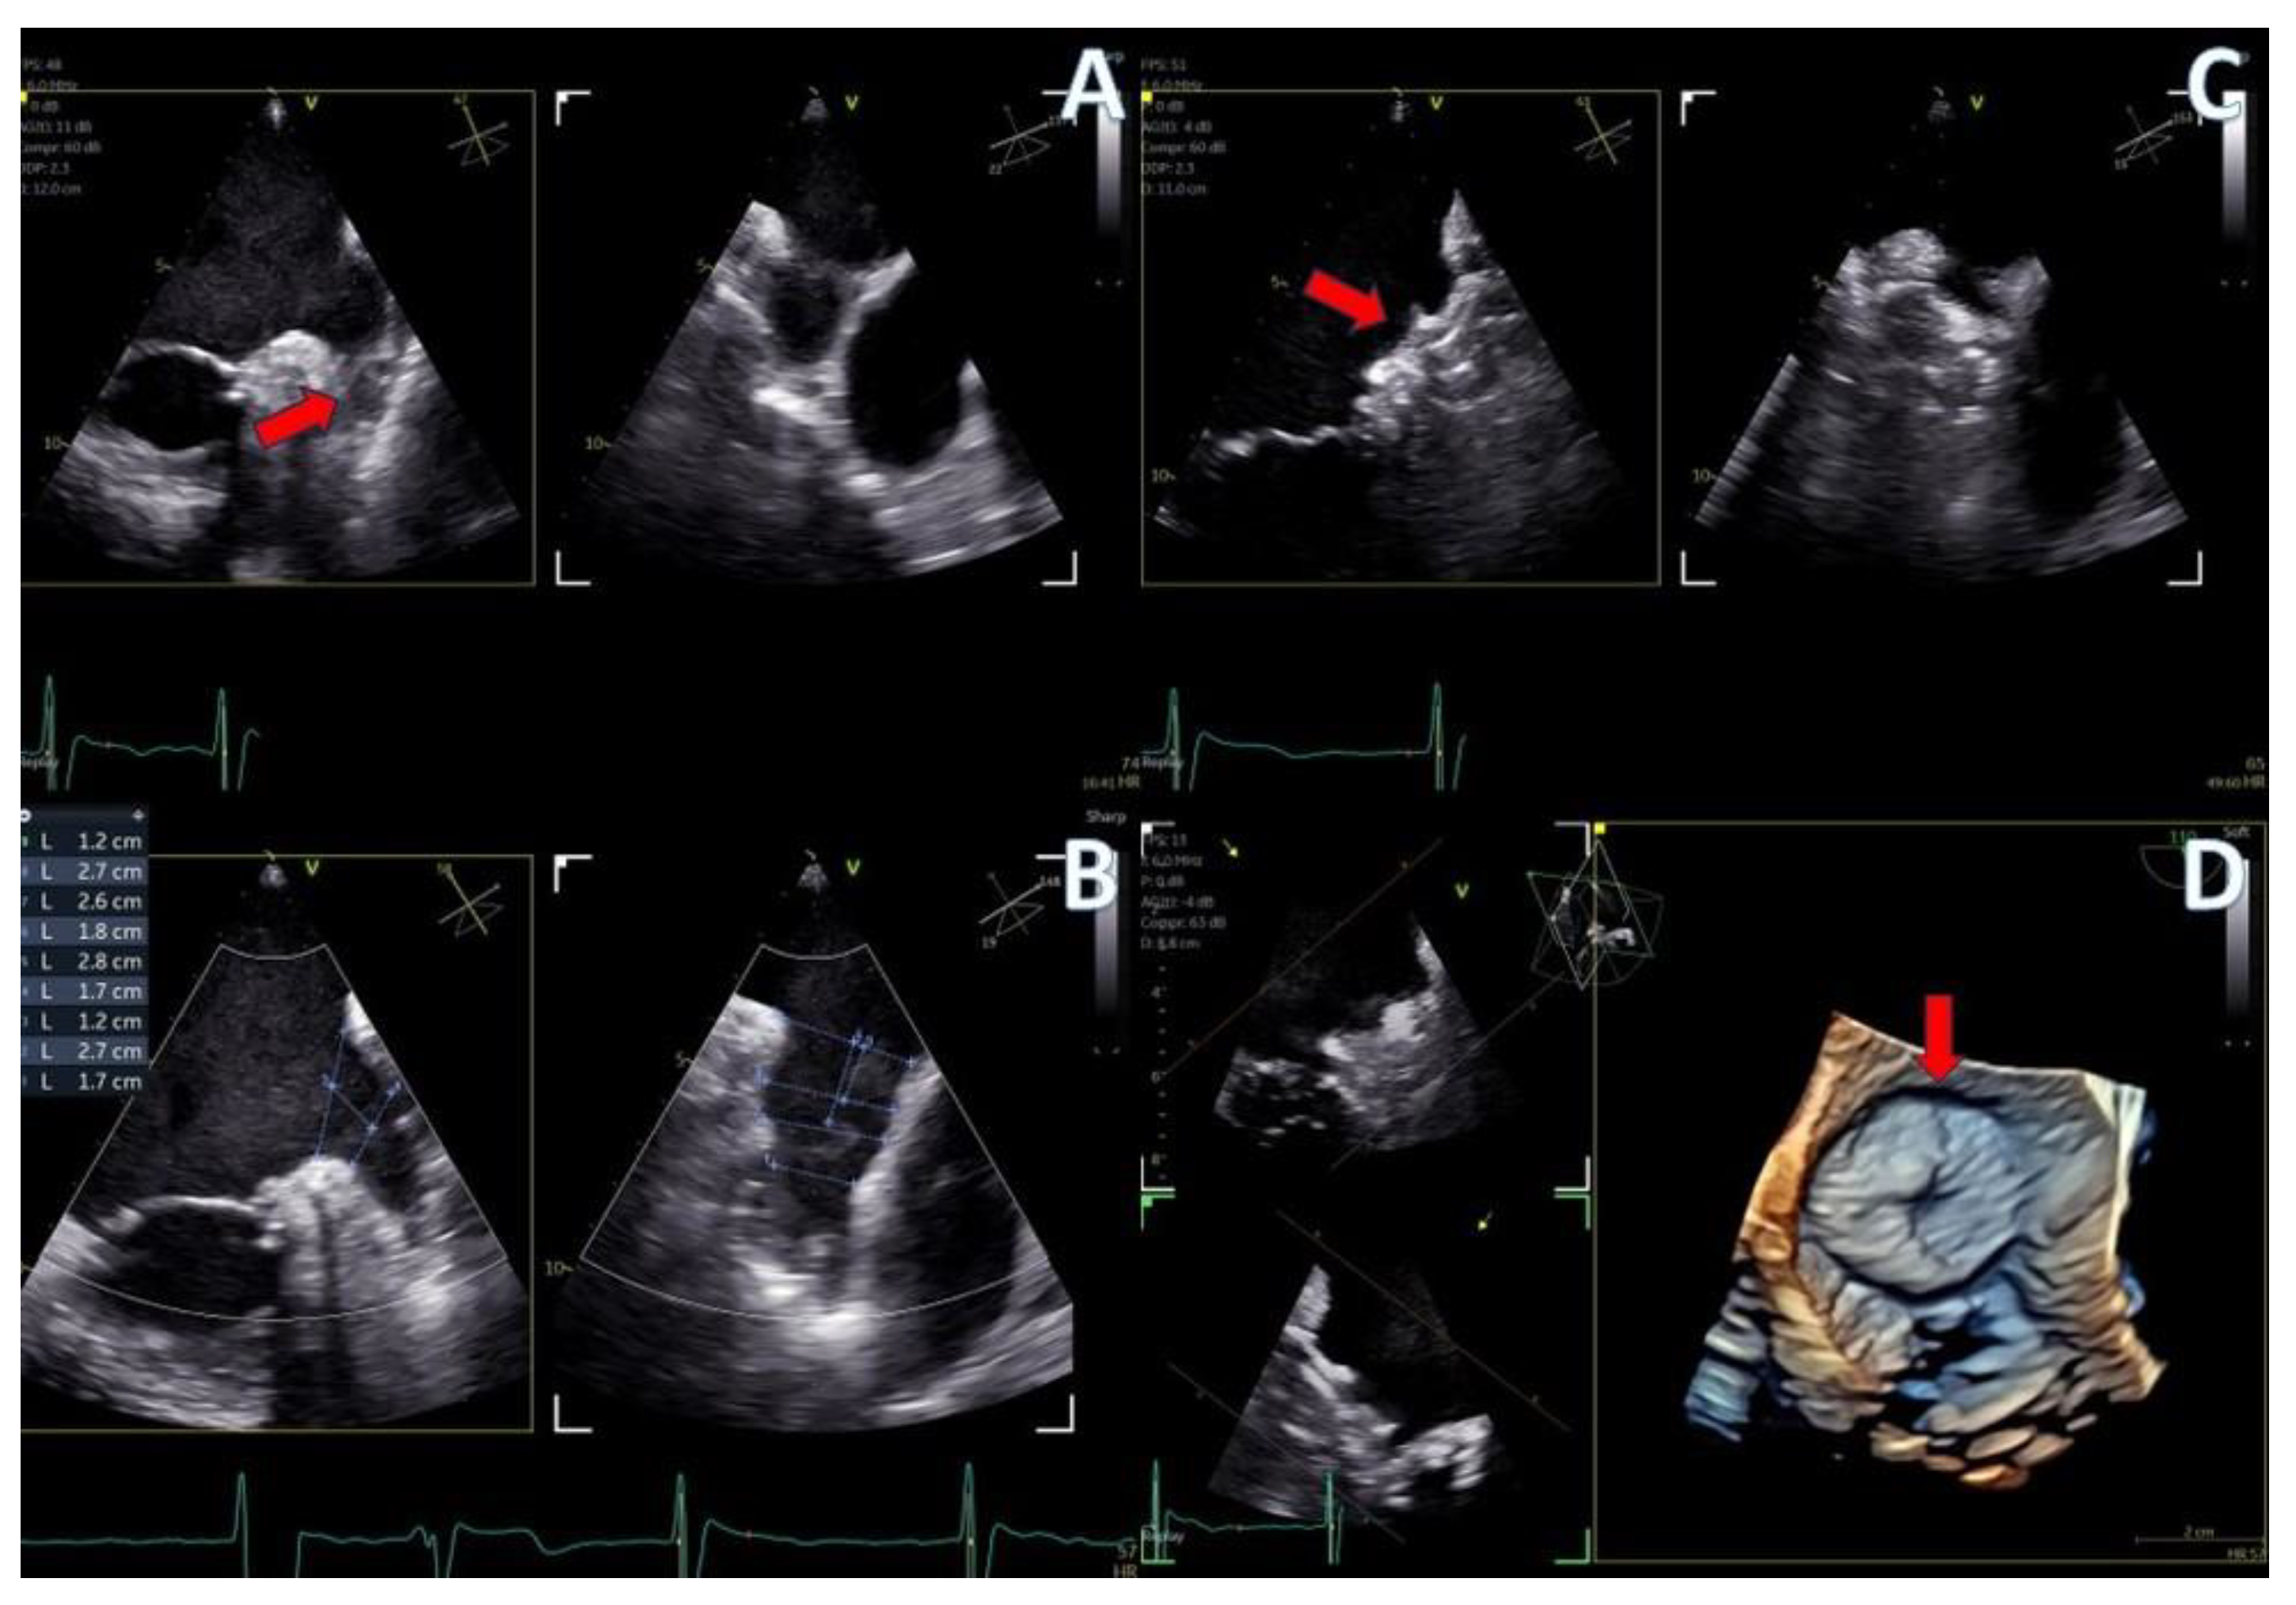

Figure 7.

Secundum ASD closure case; (A) Flexislice method for measurements with both 2D and 4D images, (B) guide catheter through the defect (red arrow), (C) biplane 2D images showing the implanted ASD occluder, (D) 3D volume-−rendered image showing the final result with an ASD occluder.

Figure 8.

LAA closure case; (A) biplane images of the LAA showing the presence of distal thrombus (red arrow), (B) measurements of the ostium and the landing zone with biplane imaging, (C) Biplane images of the implanted AMULET device (red arrow), (D) 3D volume−rendered image showing a view of the implanted AMULET device (red arrow).

In the case of LAA closure (Figure 8, video S3), 3D tools (MPR-flexislice) aided in accurate sizing of the ostium and the landing zone (important for AMULET device), particularly in the presence of distal thrombus where contrast infusion was contraindicated. The final result was satisfactory, with no leakage observed and a stable device placement was confirmed with a tug test.

PFO closure cases (Figure 9, video S2) benefited from the probe’s excellent imaging, enabling precise wire insertion and providing anatomical criteria for device sizing. A bubble contrast study was performed at the beginning and at the end of the procedure for any remaining shunt. The stability of the device was confirmed with a wiggle test. Similarly, in the ASD case (Figure 7, video S1), the probe facilitated visualization of all defect rims and accurate sizing of the oval-shaped defect (with MPR) confirmed with balloon sizing and stop-flow technique and ensured a successful outcome with no residual shunt observed.